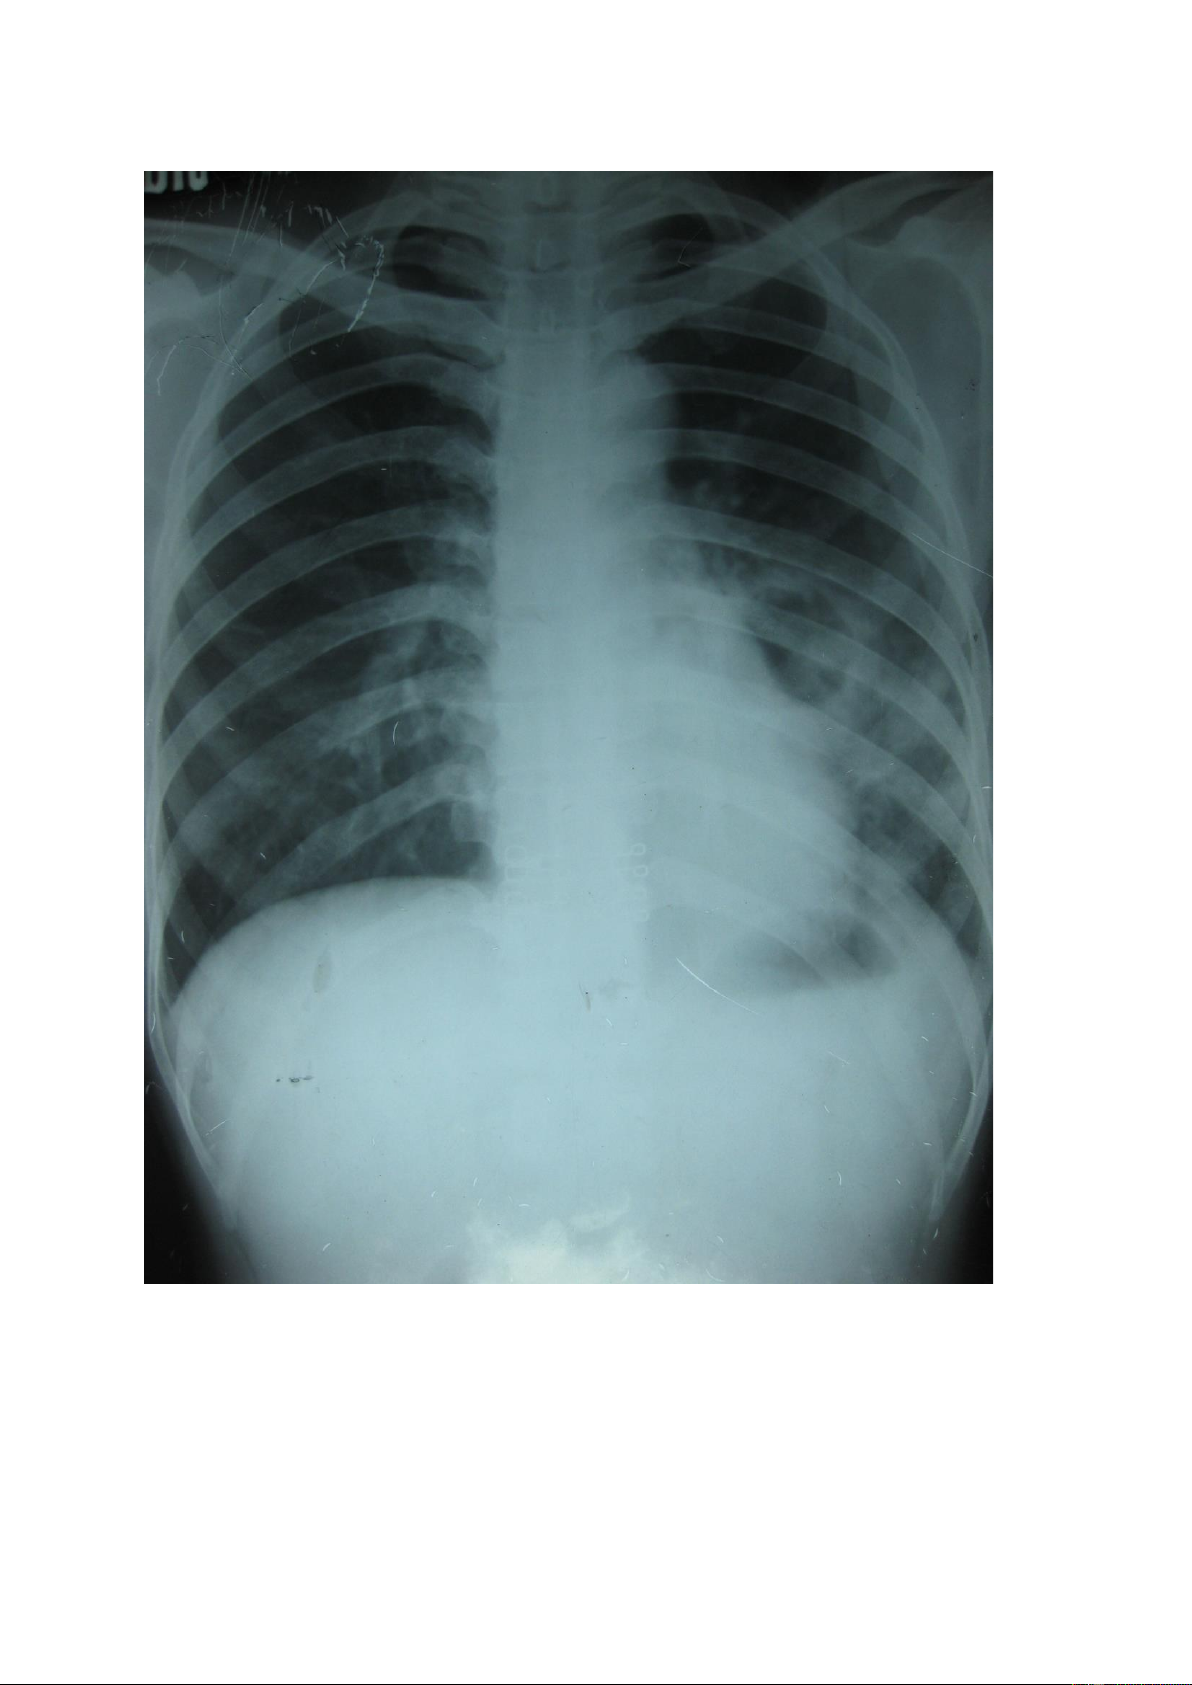

2. Tổn thương quá sáng

Là hình ảnh tổn thương có màu đen hơn mô phổi lành xung quanh. Nếu tổn thương có nhìn

thấy mạch máu đi qua chứng tỏ thuộc vùng mô phổi, nếu tổn thương sát với bờ ngoại vi phổi

không thấy phân bố mạch máu bên trong thường gặp trong tràn khí khoang màng phổi. lOMoAR cPSD| 22014077

2.2. Quá sáng do tràn khí màng phổi